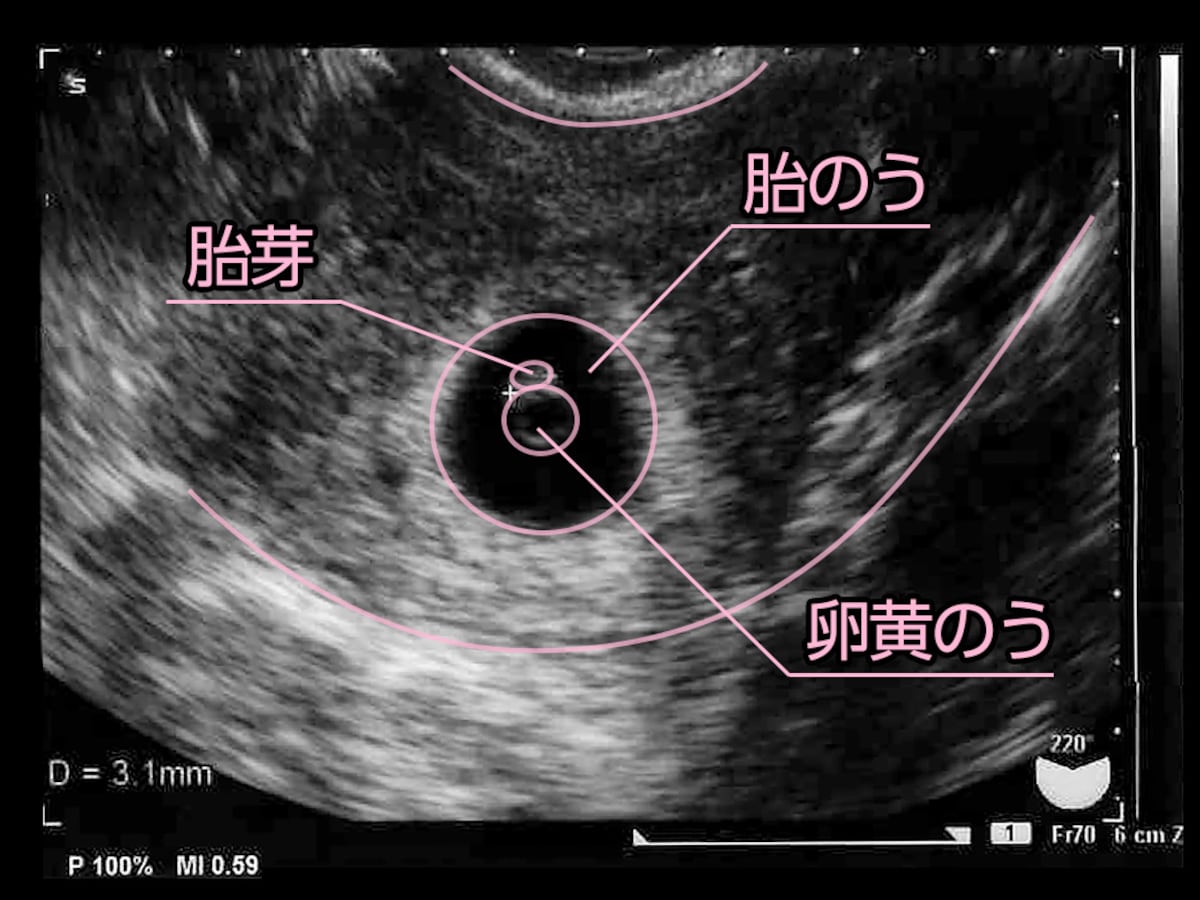

初めてパパ用 胎嚢 たいのう 超音波エコー検査の見方 6週0日 プレパパ獣医 子供と猫とrichになるブログ

5 産科一般超音波検査 初期編 正常所見4 7週 日本産婦人科医会

妊娠2ヶ月 妊娠4週0日 7週6日 の胎芽の超音波画像 2 超音波画像で見る妊娠各月の胎児

医療監修 胎嚢 たいのう とは 確認方法や確認できる時期を知ろう ママリ

妊娠6週目 エコー写真 胎芽や胎嚢大きさ 心拍確認や気になる流産 妊娠初期 All About